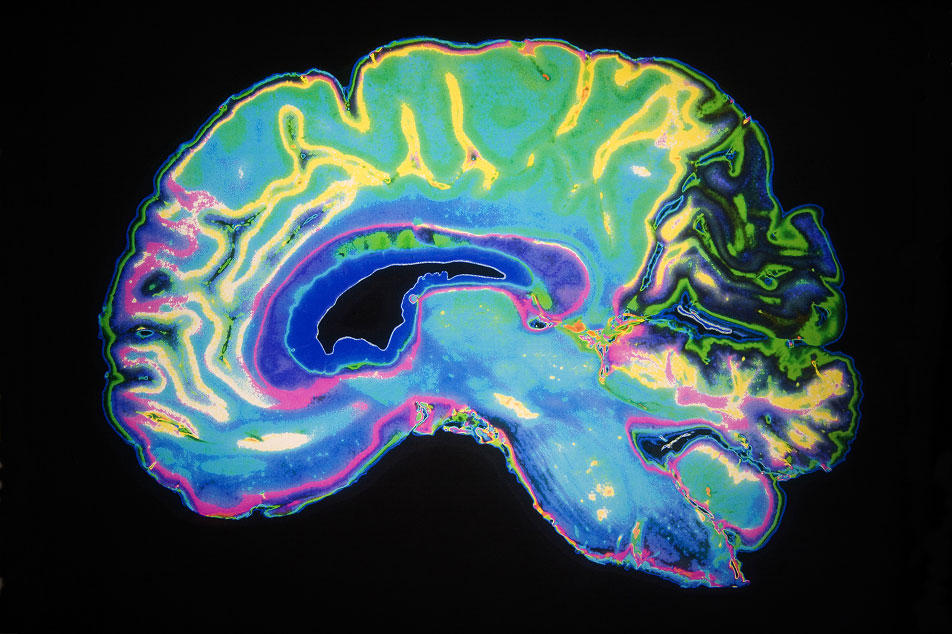

Unlocking the brain’s secrets: How epilepsy genes affect different regions

Thanks to a study using advanced 3D brain models, scientists at UCLA Broad Stem Cell Research Center discovered that a single gene variant can cause a variety of developmental problems often seen alongside epilepsy. These stem cell-derived models could become a vital tool for developing treatments for epilepsy and other cognitive and behavioral challenges.

MRIs, Mozart and the wonders of mathematics

If you’ve had an MRI in recent years, you have UCLA mathematician and Fields Medal winner Terence Tao to thank for the technology. His foundational work in compressed sensing, conducted with Stanford professor Emmanuel Candès, paved the way for clinical techniques that use complex algorithms to create amazingly precise images from a tiny amount of data — cutting down the time and cost of the process and expanding its availability.